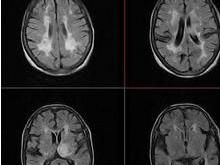

2.MR表現:

可更好地顯示皮質下動脈硬化性腦病,主要在T2加權圖像上表現為兩側側腦室旁、中央半卵圓區白質內較廣泛班片狀及點狀高信號,同時伴基底節-內囊區、腦幹的斑點狀高信號。在 T1加權圖像上以上病灶多不明顯,表現為等信號。